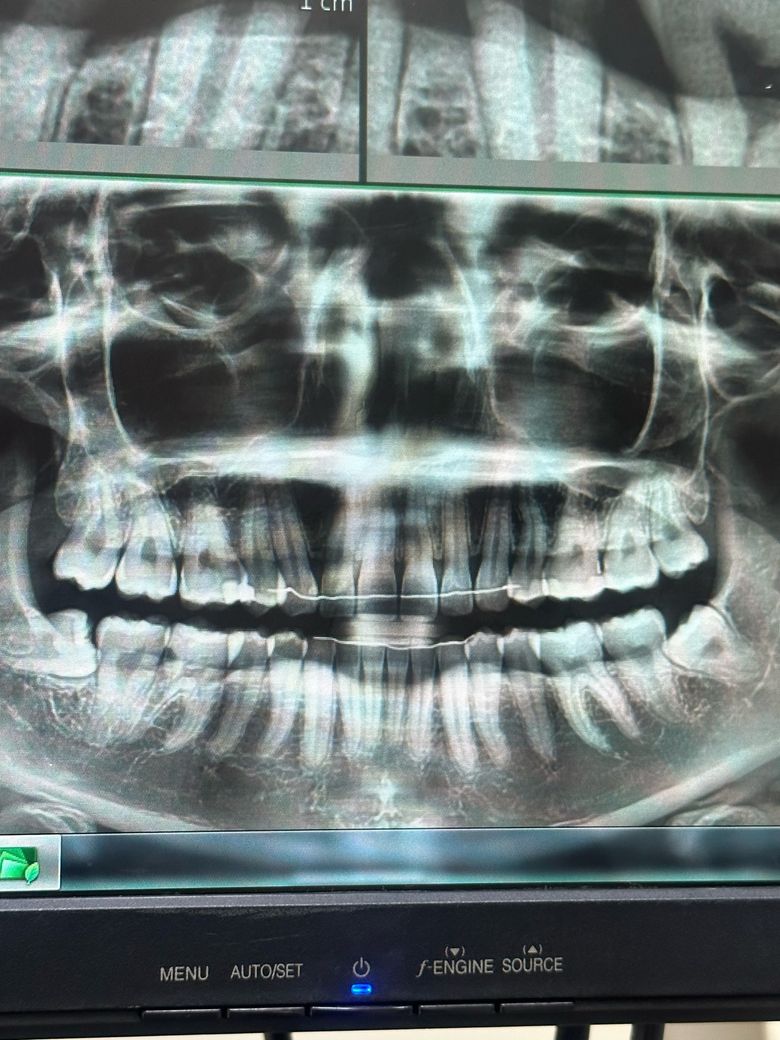

사진상 왼쪽 아래 ( 실제로는 오른쪽입니다) 아래 매복니에 음식물이 너무 많이 끼고 아파서 무조건 뽑을 예정입니다. 근데 혹시 그 위 사랑니도 (매복 아니고 똑바로 잘 났습니다) 같이 뽑아야할까요? 같이 뽑는 게 좋을까요??

이게 그 옆 어금니랑 같이 저작기능을 할 수 도 있어서 안 뽑는 게 좋을지 궁금합니다..! 사진상에서는 어금니랑 사랑니랑 교합하지 않는 것처럼 보이지만 저게 단면 파노라마 사진이라.. 궁금합니다

이미 교정 때문에 윗니만 발치 2개를 한 상황이라 balance를 맞추려면 아래만 뽑는 것도 좋을 것 같고ㅜ 사랑니까지 발치하면 너무 적은 치아 개수로 살아가야하는 것 같아서요

• 2번 째 사진